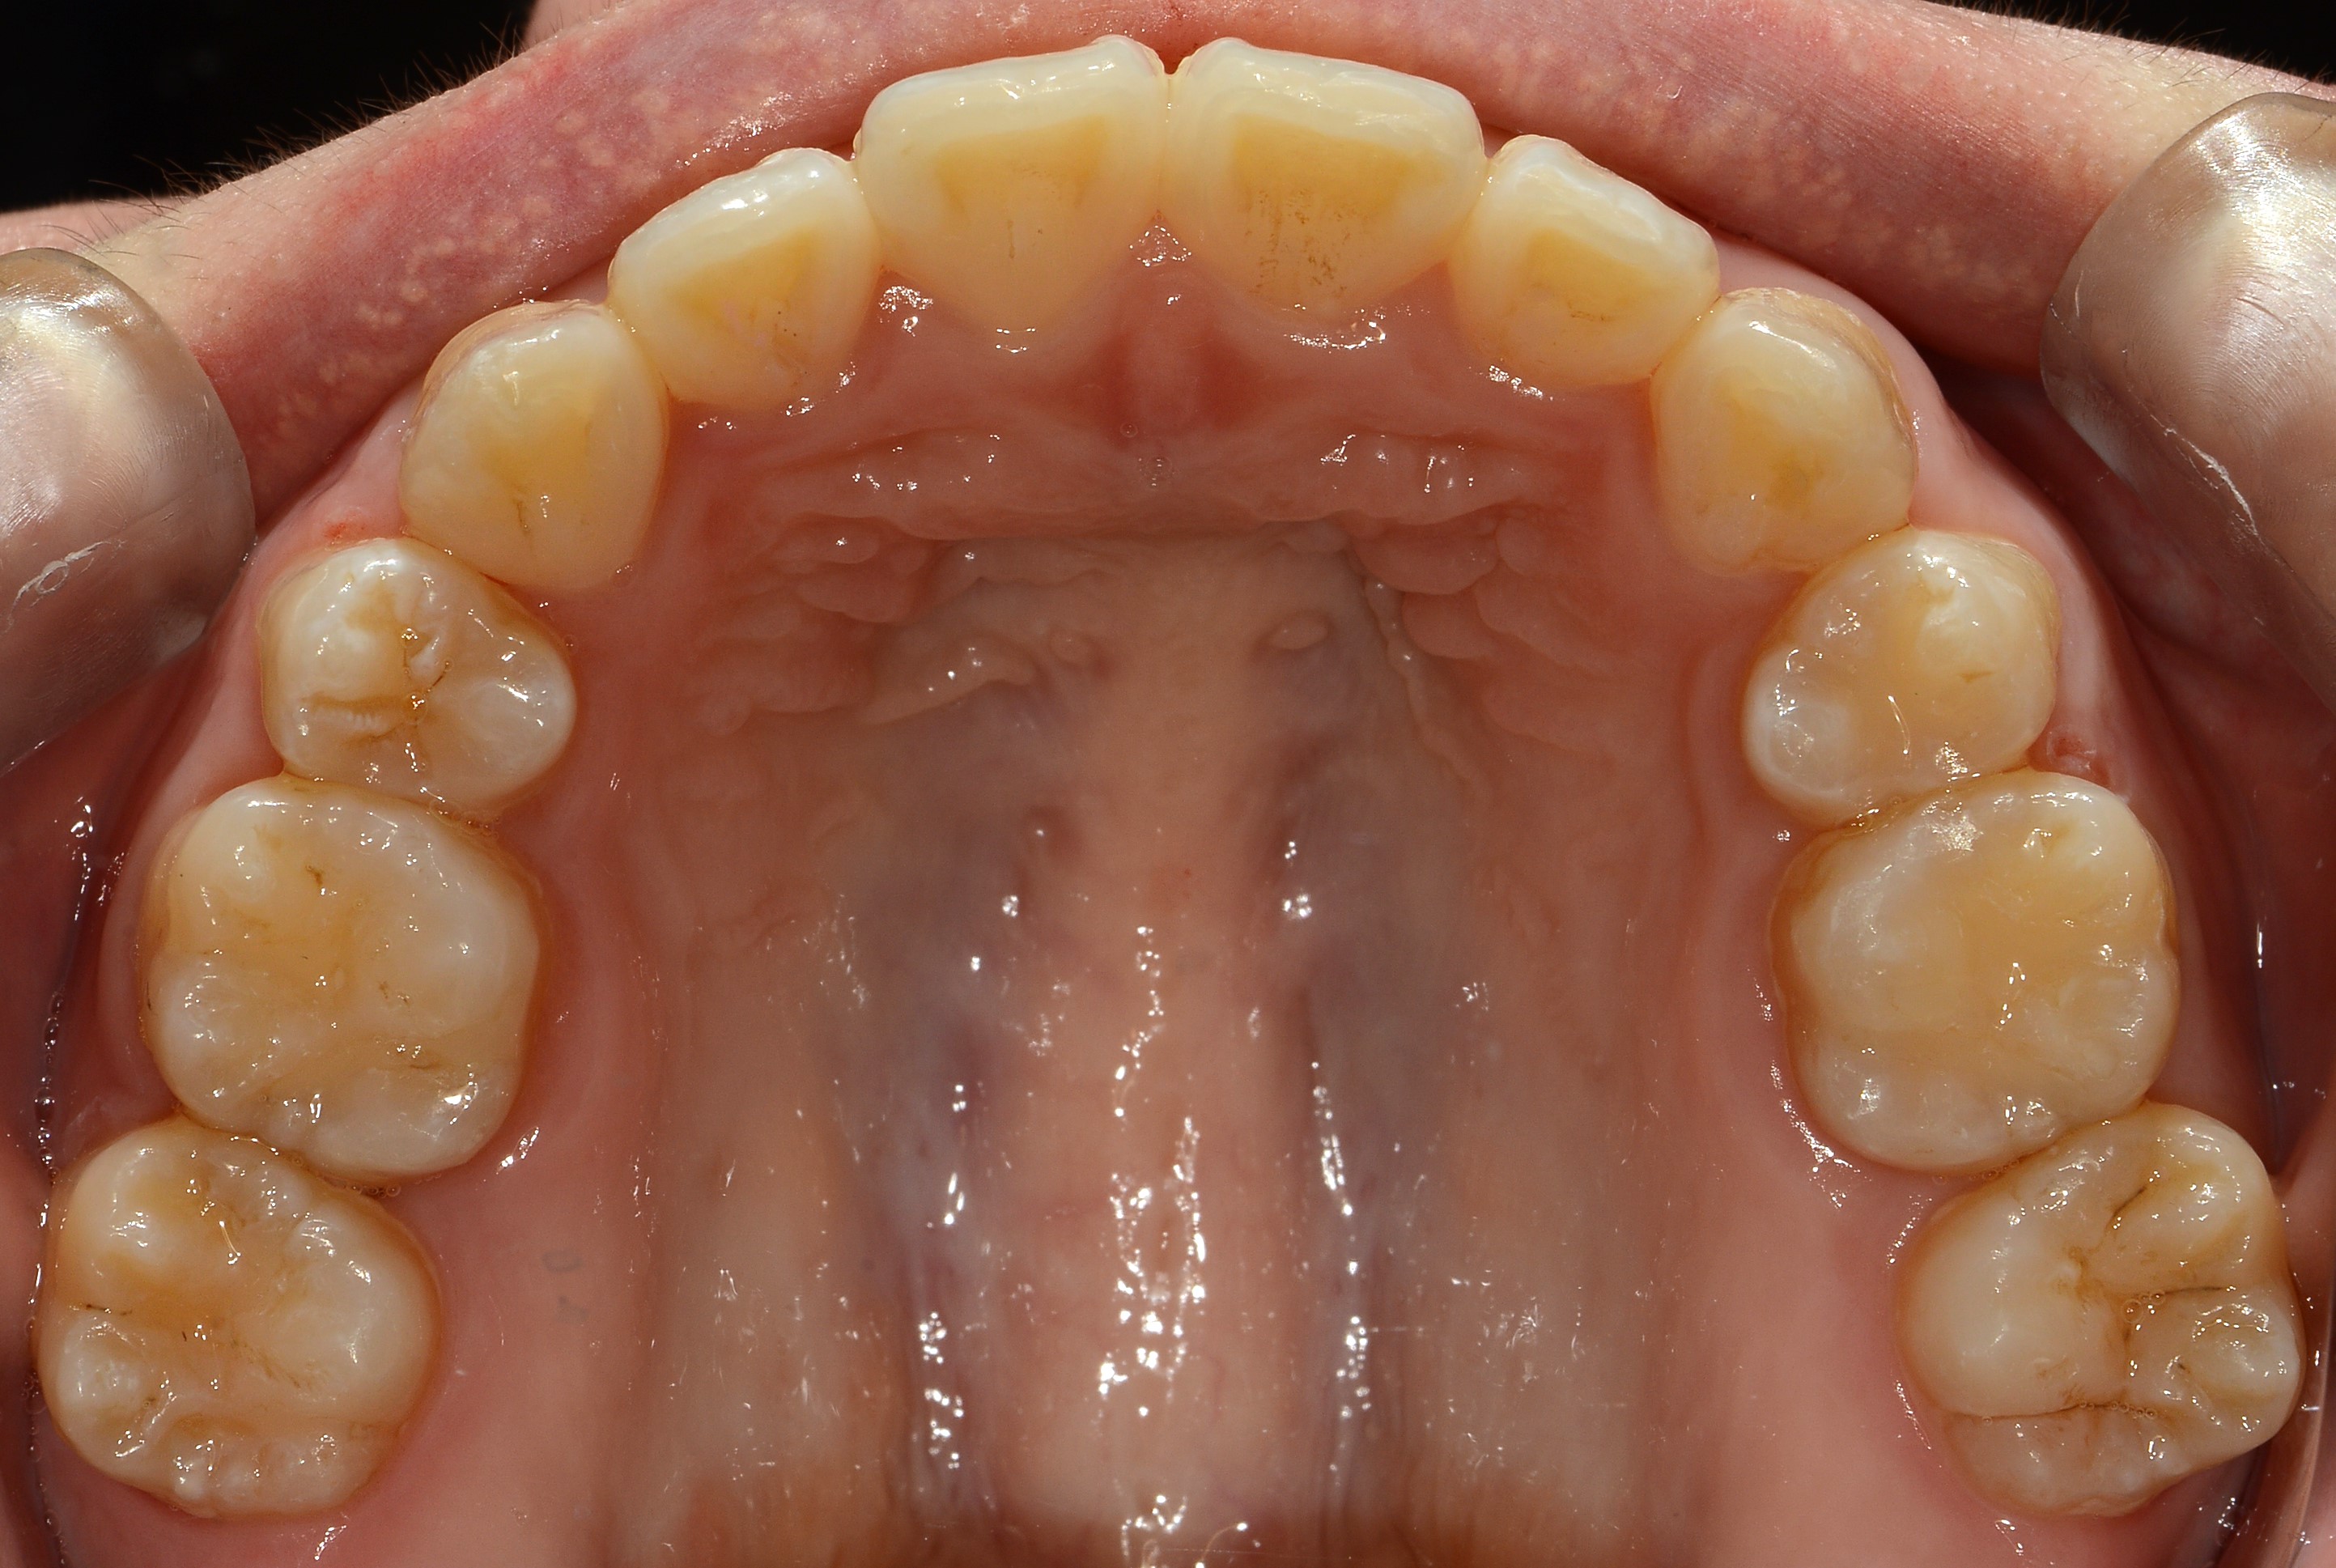

치료 후 사진입니다.